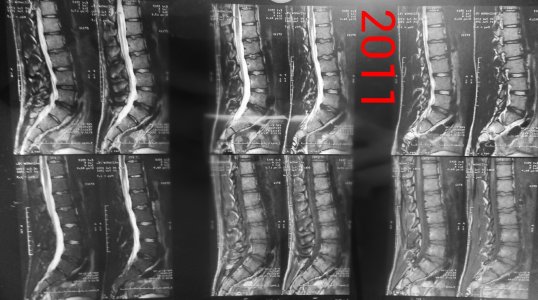

Здравствуйте! Я парень, мне 21 год, рост 190, вес 90, у меня поясничные грыжи l1-l2 1,8 мм, l2-l3 3,5 мм, l5-s1 4,4 мм, беспокоит уже 1,5 года слабость в ногах сначала была боль в левой ноге затем исчезла, и появилась постепенно слабость с внешней стороны квадрицепса до большого пальца ноги, и справа от колена по внешней стороне до большого пальца вниз, больше интересует непостоянность этих симптомов, то есть они могут вообще исчезать на один день и появляться на другой, могут появиться просто когда лежал телевизор смотрел и при этом спина вообще не болит, и в ногах боли тоже нет, невролог проводивший осмотр направлял на вич, гепатит, сифилис все чисто. Если начинаю пить прозерин по 2 таблетки в день все как рукой снимает. Ниже приведены все снимки и заключения имеющиеся на руках.Что это может быть, почему слабость может так быстро исчезать и появляться снова, грыжи то на месте может это что то другое? И еще хотелось бы узнать ваше мнение по поводу записи в заключении 2013 года (Арахноидальная киста в мягких тканях на уровне межостистых отростков L5-S1 7x8-8x2 мм) она не может сдавливать нервы?